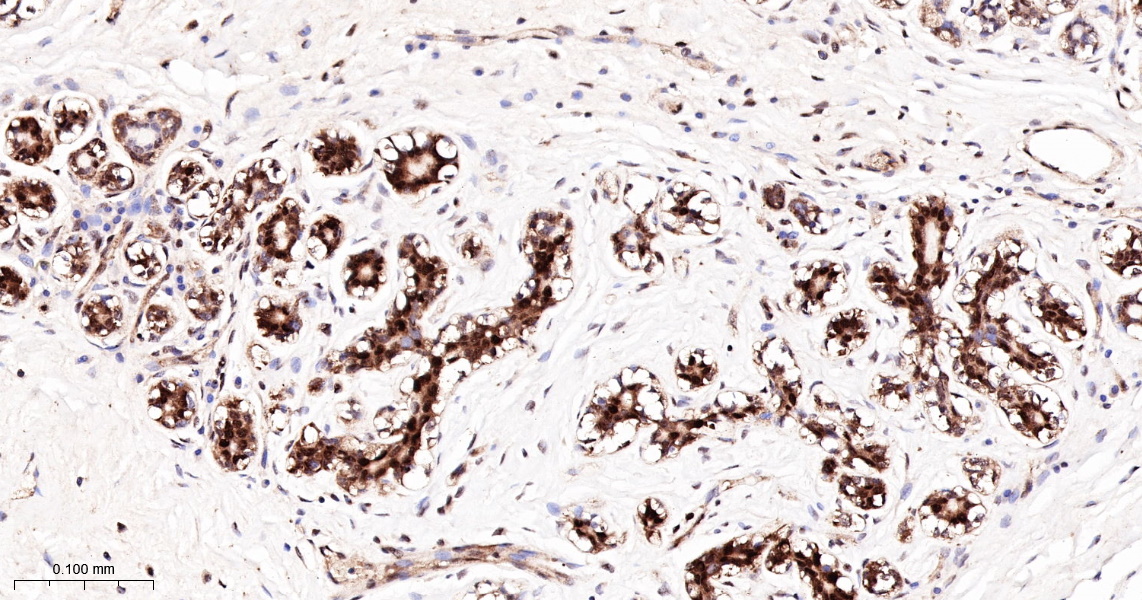

IHC-P 1:200-400